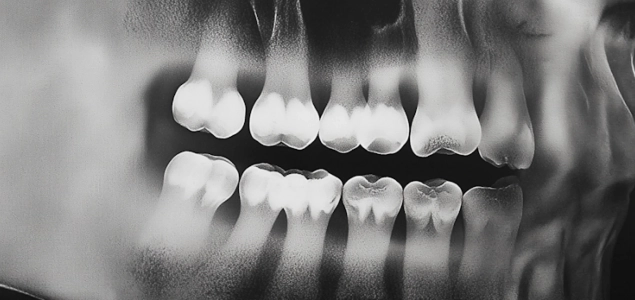

Dental Treatments: A Guide to Oral Health